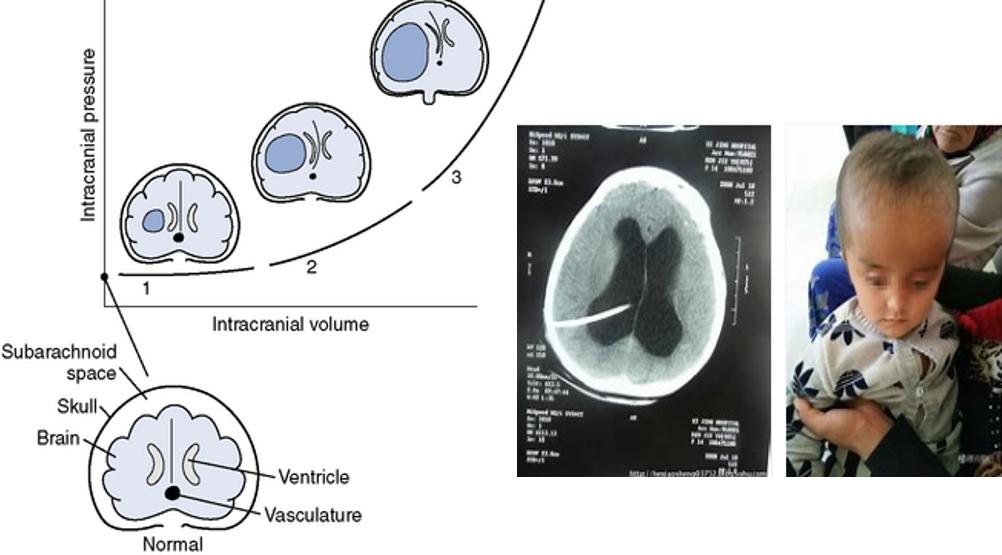

还有我们老百姓知道的脑积水,脑积水它是因为脑内有一些保护我们脑组织输送营养、润滑细胞之间的液体,我们叫脑脊液。那么脑脊液它两种,一个是它排不出去了,就像家里的下水管子堵了,一定会把水池子堵上;还有一种水池子下水每分钟只能下10毫升,但是我们开巨大的管子,1分钟可以1万毫升,那就相当于分泌多了,它就会造成脑积水,脑脊液多了,出不去或是分泌多了,小不点的孩子就会出现大脑袋,所以我用了一个脑积水的一级、二级、三级来表示:

大家可以看到灰蓝色的越大,脑积水越厉害,所以孩子也会表现为呕吐。如何发现脑积水的这个情况是被占位、被颅压高导致非常容易,做一个影像学的片子,比如做一个CT、做一个磁共振,就可以看到脑子里长没长瘤子、有没有出血、有没有压力高造成脑积水,这个问题就非常容易地解决了。